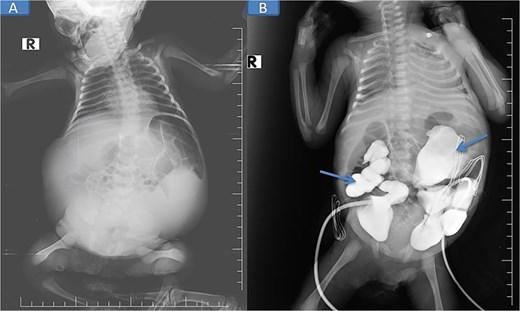

Abdominal and scrotal ultrasonography demonstrated multilocular cystic hydronephrosis with thinning of renal parenchyma, extending into the pelvis, and absence of testes within the scrotum. Both testes were located intra-abdominally between bowel loops (left 7 × 4.5 mm, right 6 × 5.5 mm) (Figs 2 and 3). Abdominal X-ray after percutaneous nephrostomy with contrast revealed pooling in both kidneys without ureteric passage, suggesting bilateral ureteropelvic junction obstruction (UPJO) (Fig. 4).

Pre-op abdominal X-ray (A) and post-operative percutaneous nephrostomy procedure with contrast injection through the nephrostomy (B).

The patient was stabilized with CPAP oxygen, intravenous antibiotics (ampicillin, cefotaxime, metronidazole), and supportive care. Following preoperative evaluation and parental consent, bilateral nephrostomy was performed, yielding significant urine drainage. Postoperatively, renal function improved with normalization of creatinine and urea, and by Day 5 post-nephrostomy, values had returned to normal (urea 13 mg/dl [reference: 10–45] and creatinine 0.48 mg/dl [reference: 0.35–1.10]), accompanied by a reduction in abdominal distention.